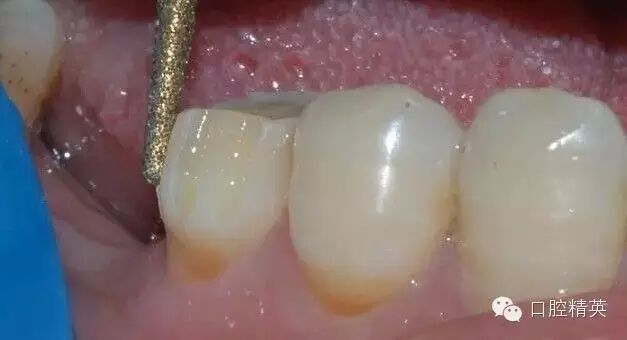

鄰面的制備,先用較細的金剛砂車針貼基牙鄰面制備,勿損傷鄰牙